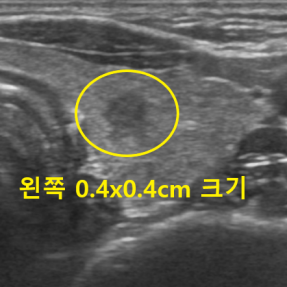

Thyroid Clinic

갑상선 클리닉